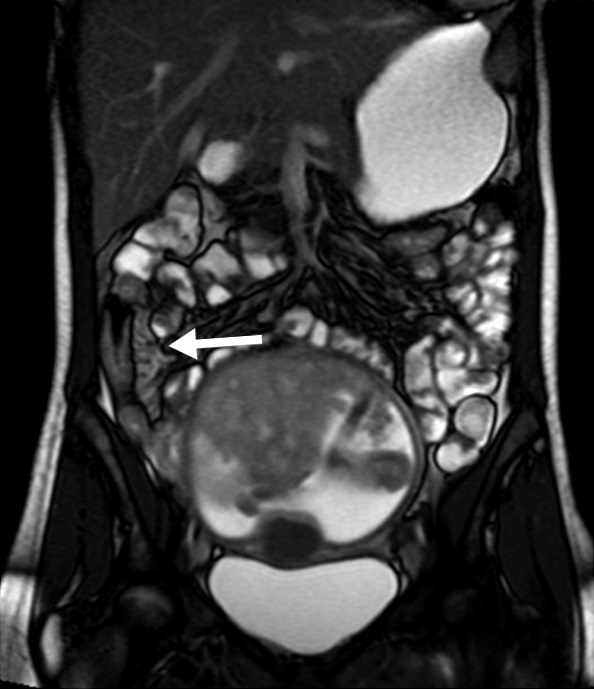

Figura 2

Paciente de sexo masculino de 9 años con antecedente de resección colónica y ostomía por enfermedad de Crohn. a) Secuencia eco de gradiente coronal donde se idenjpgica el engrosamiento parietal del asa detransitada de 6 mm de espesor (punta de flecha).

b) Misma secuencia muestra adenomegalias ileocólicas de hasta 10 mm como elemento de actividad (punta de flecha).

c) Secuencia T2 axial con saturación grasa evidencia edema submucoso como una banda hiperintensa central entre la mucosa y serosa (flecha).